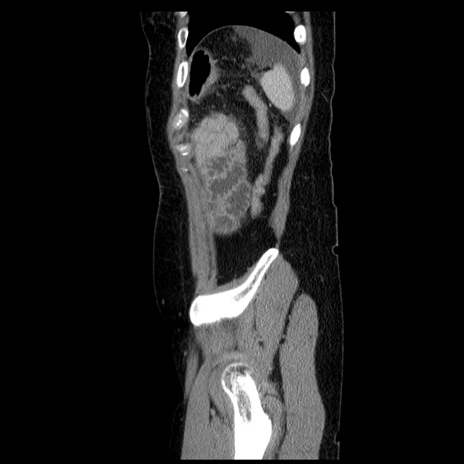

横断像